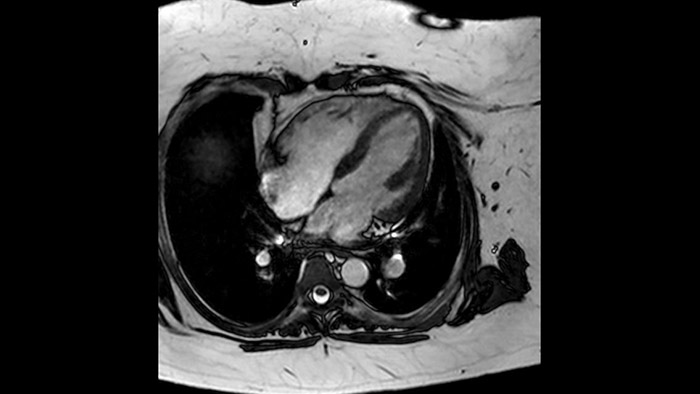

Comprehensive cardiac MR imaging

Diagnostic and prognostic utility of cardiac MR is increasing. Assess the anatomy and function of the heart using cine acquisitions, acquire information about perfusion and viability of the cardiac tissue, visualise potential edema with black blood sequence, access and even quantify tissue characterisation with CardiacQuant.

Quantify Myocardial Strain

IntelliSpace Portal MR Caas5,6 Strain7 assists in patient diagnosis and monitoring by providing global strain parameters such as global longitudinal strain (GLS), global circumferential strain (GCS), and global radial strain (GRS), using short and long axis MR images, as well as describing the myocardium deformation- such as shortening, thickening, and lengthening during the cardiac cycle.